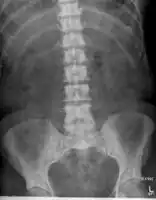

Sclerosis of the bones of the pelvis due to prostate cancer metastases